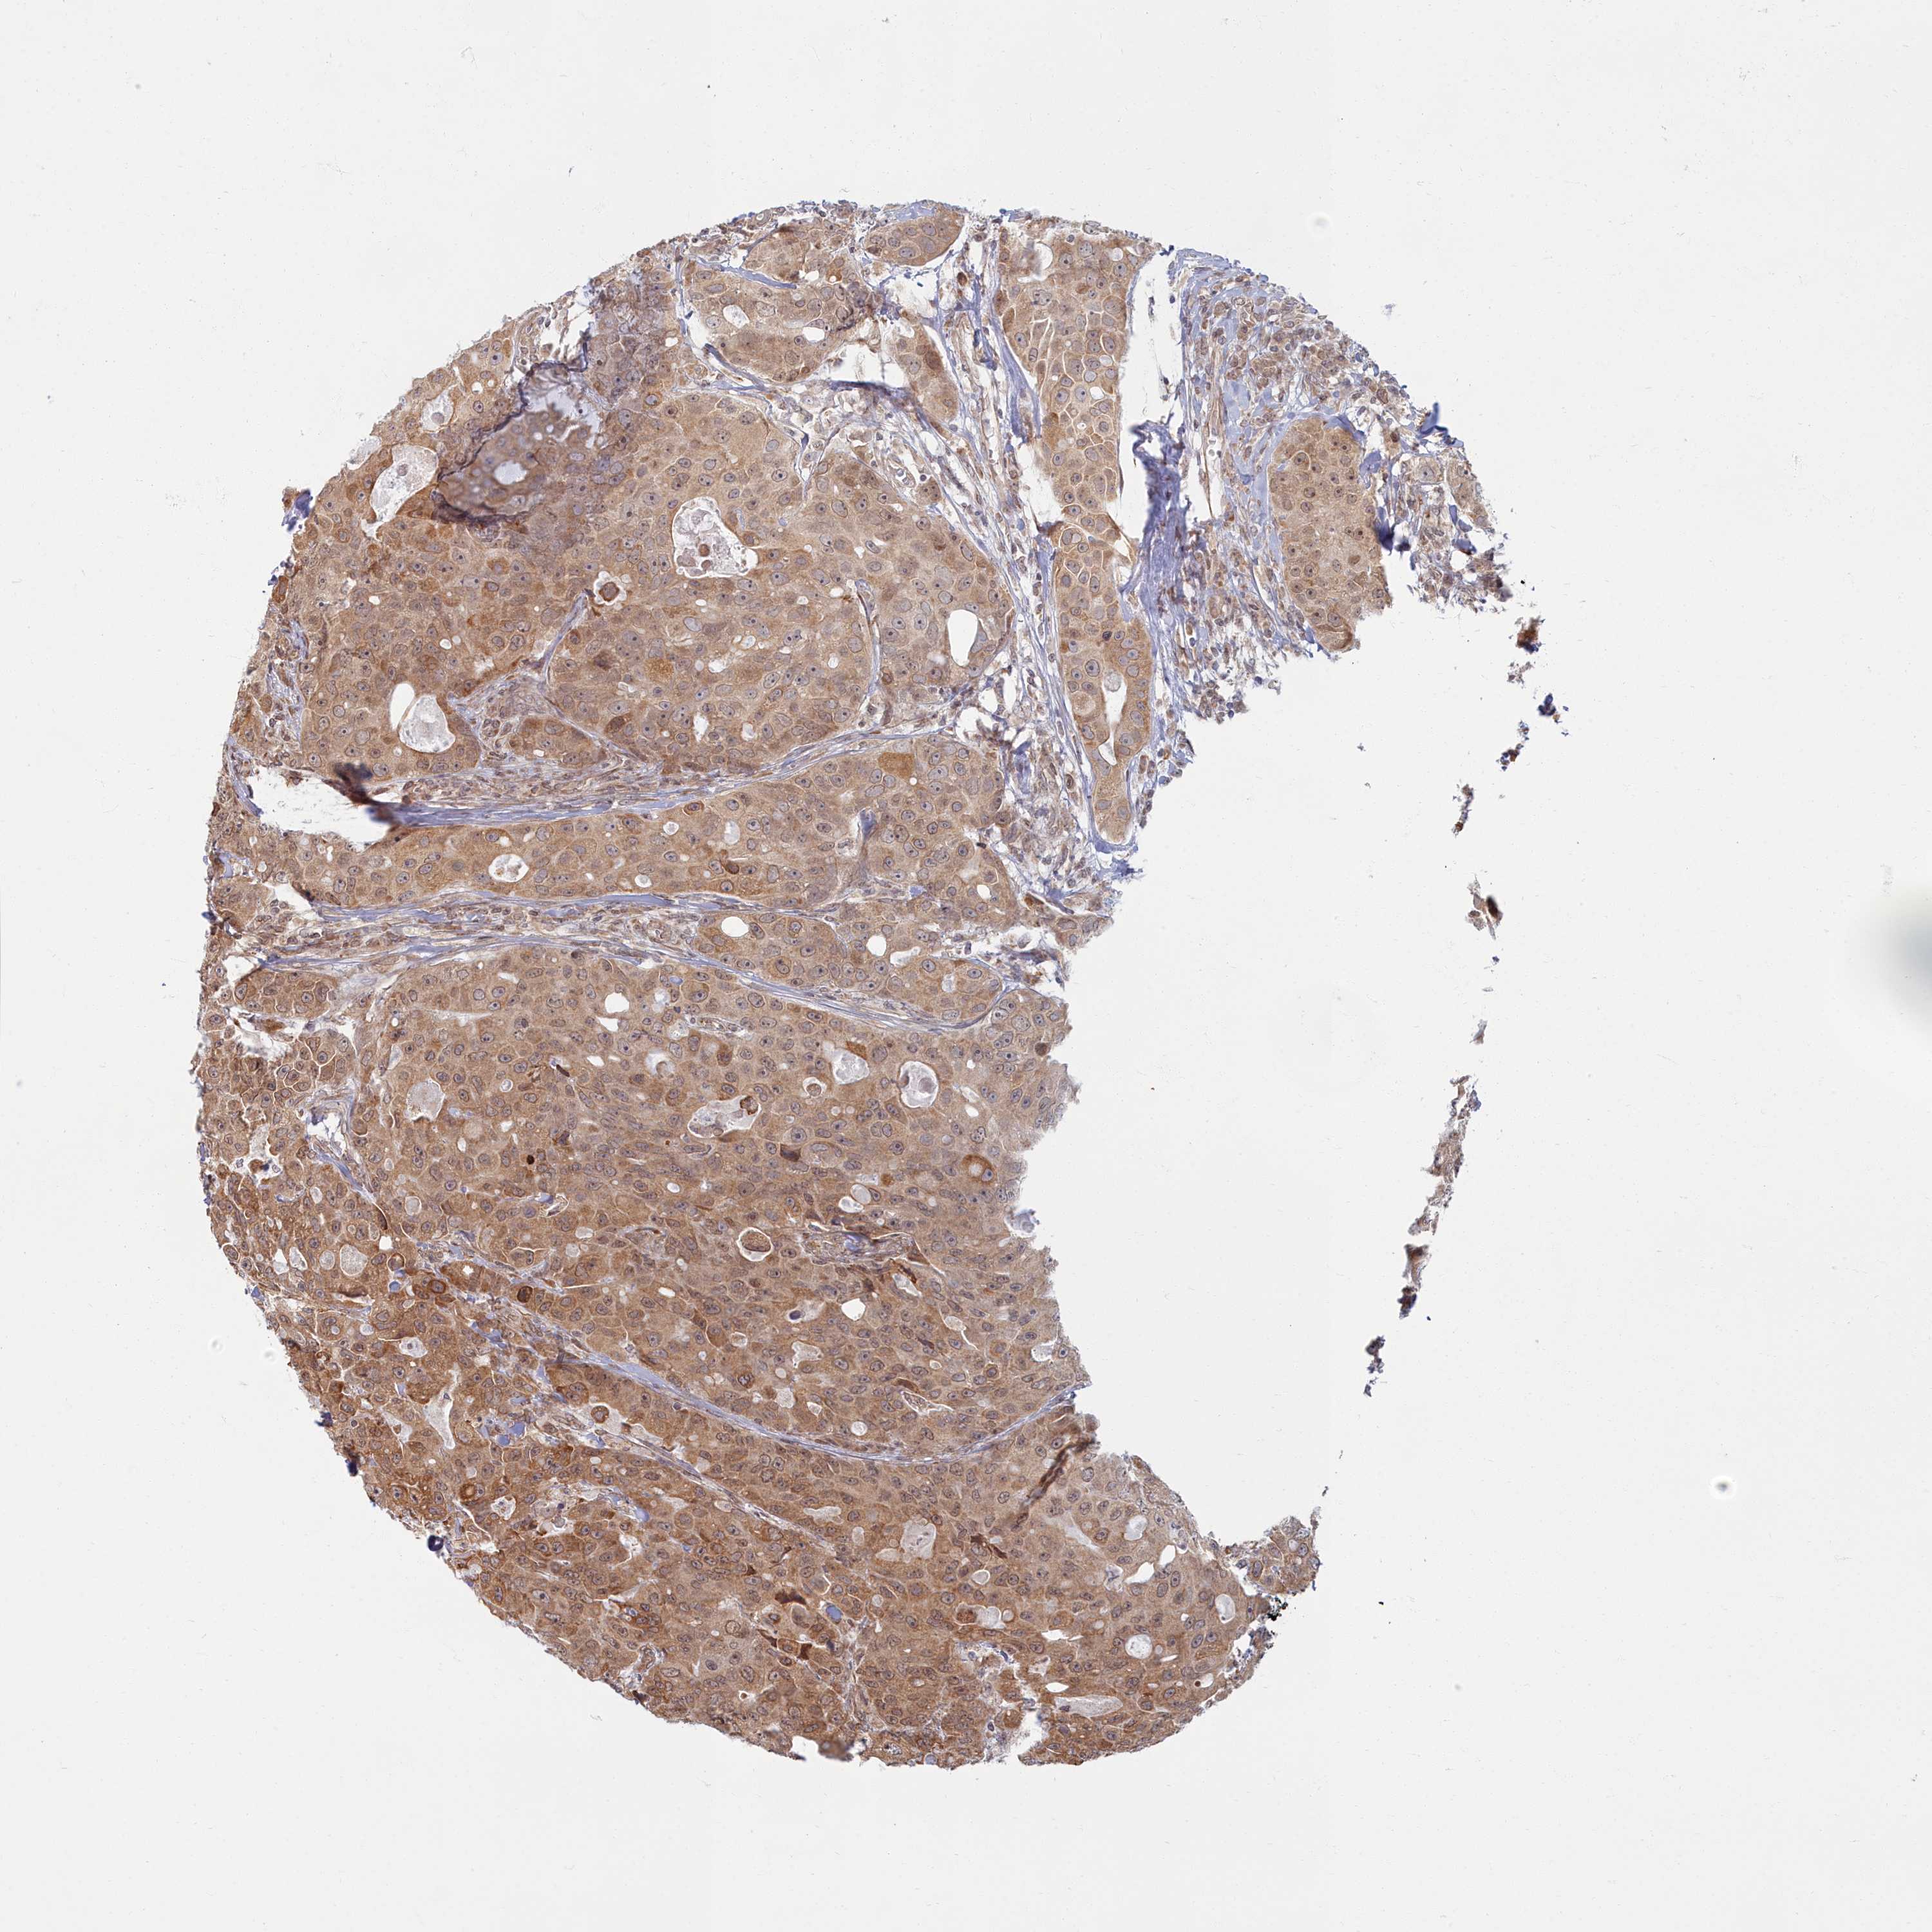

CANCER BREAST CANCER Show tissue menu

BRCA TCGA BRCA VALIDATION PROTEIN EXPRESSION